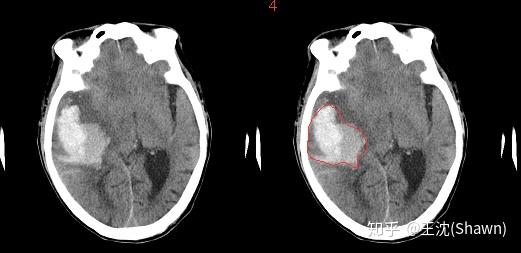

1.图像语义较为简单、结构较为固定。我们做脑的,就用脑CT和脑MRI,做胸片的只用胸片CT,做眼底的只用眼底OCT,都是一个固定的器官的成像,而不是全身的。由于器官本身结构固定和语义信息没有特别丰富,所以高级语义信息和低级特征都显得很重要(UNet的skip connection和U型结构就派上了用场)。举两个例子直观感受下。

A.脑出血. 在CT影像上,高密度的区域就大概率是一块出血,如下图红色框区域。